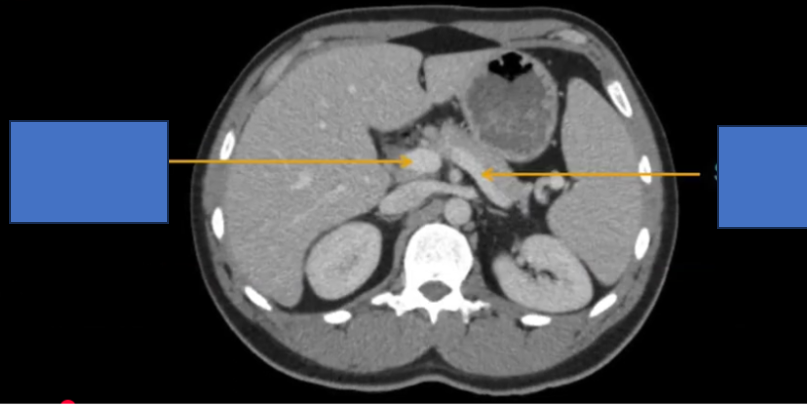

TM gan ở đâu? TM chủ dưới ? ĐM chủ?